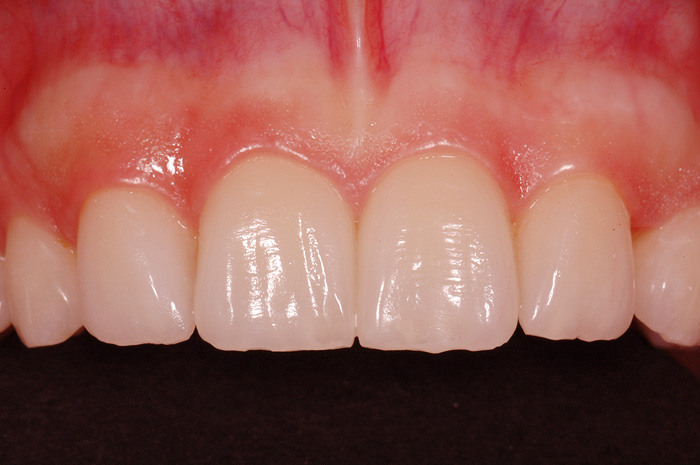

Fallbeispiel

Zum Vergrössern klicken